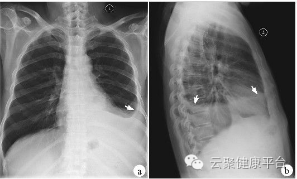

3、胸部——粗看X光片,细看CT

X光胸片可粗略检查心脏、主动脉、肺、胸膜、肋骨等,可以检查有无肺纹理增多、肺部钙化点、主动脉结钙化等。胸部CT检查显示出的结构更清晰,对胸部病变检出敏感性和显示病变的准确性均优于常规X光胸片,特别是对于早期肺癌确诊有决定性意义。但是常规CT检查的辐射剂量高于X光(开源超炫速CT除外)。核磁对于肺部疾病的诊断,应用非常有限。